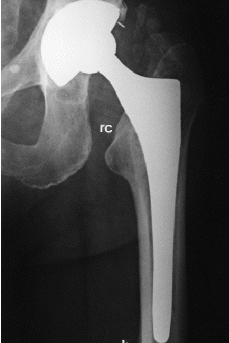

Aparte de cambios tan evidentes como la osteolisis o el hundimiento del vástago femoral, el análisis radiológico de las prótesis no cementadas ha permitido detectar una serie de signos, cuyo significado continúa siendo controvertido. Entre ellos cabe citar: líneas radiolucentes periprotésicas, redondeamiento y esponjialización del calcar, hipertrofia cortical distal, esclerosis por debajo de la punta del vástago (pedestal), ensanchamiento del canal medular, y densificación endostal adyacente a la zona de recubrimiento (puntos de soldadura). Engh y cols21 definieron el significado de estos signos radiológicos y establecieron, a partir de ellos, unos criterios que permitían definir sí la fijación de una prótesis era estable, con crecimiento óseo o fibroso, o inestable. Para estos autores, las líneas radiolucentes periprotésicas y la formación del pedestal indicarían una falta de osteointegración del implante. Por el contrario, el redondeamiento y atrofia del calcar, y la hipertrofia cortical distal, serían la expresión de fenómenos de adaptación del hueso al implante femoral (tabla 3) (Fig 2).

Figura 2. Presencia de signos radiológicos de remodelación ósea adaptativa en implante femoral de recubrimiento. rc: redondeamiento del calcar; h: hipertrofia cortical distal.